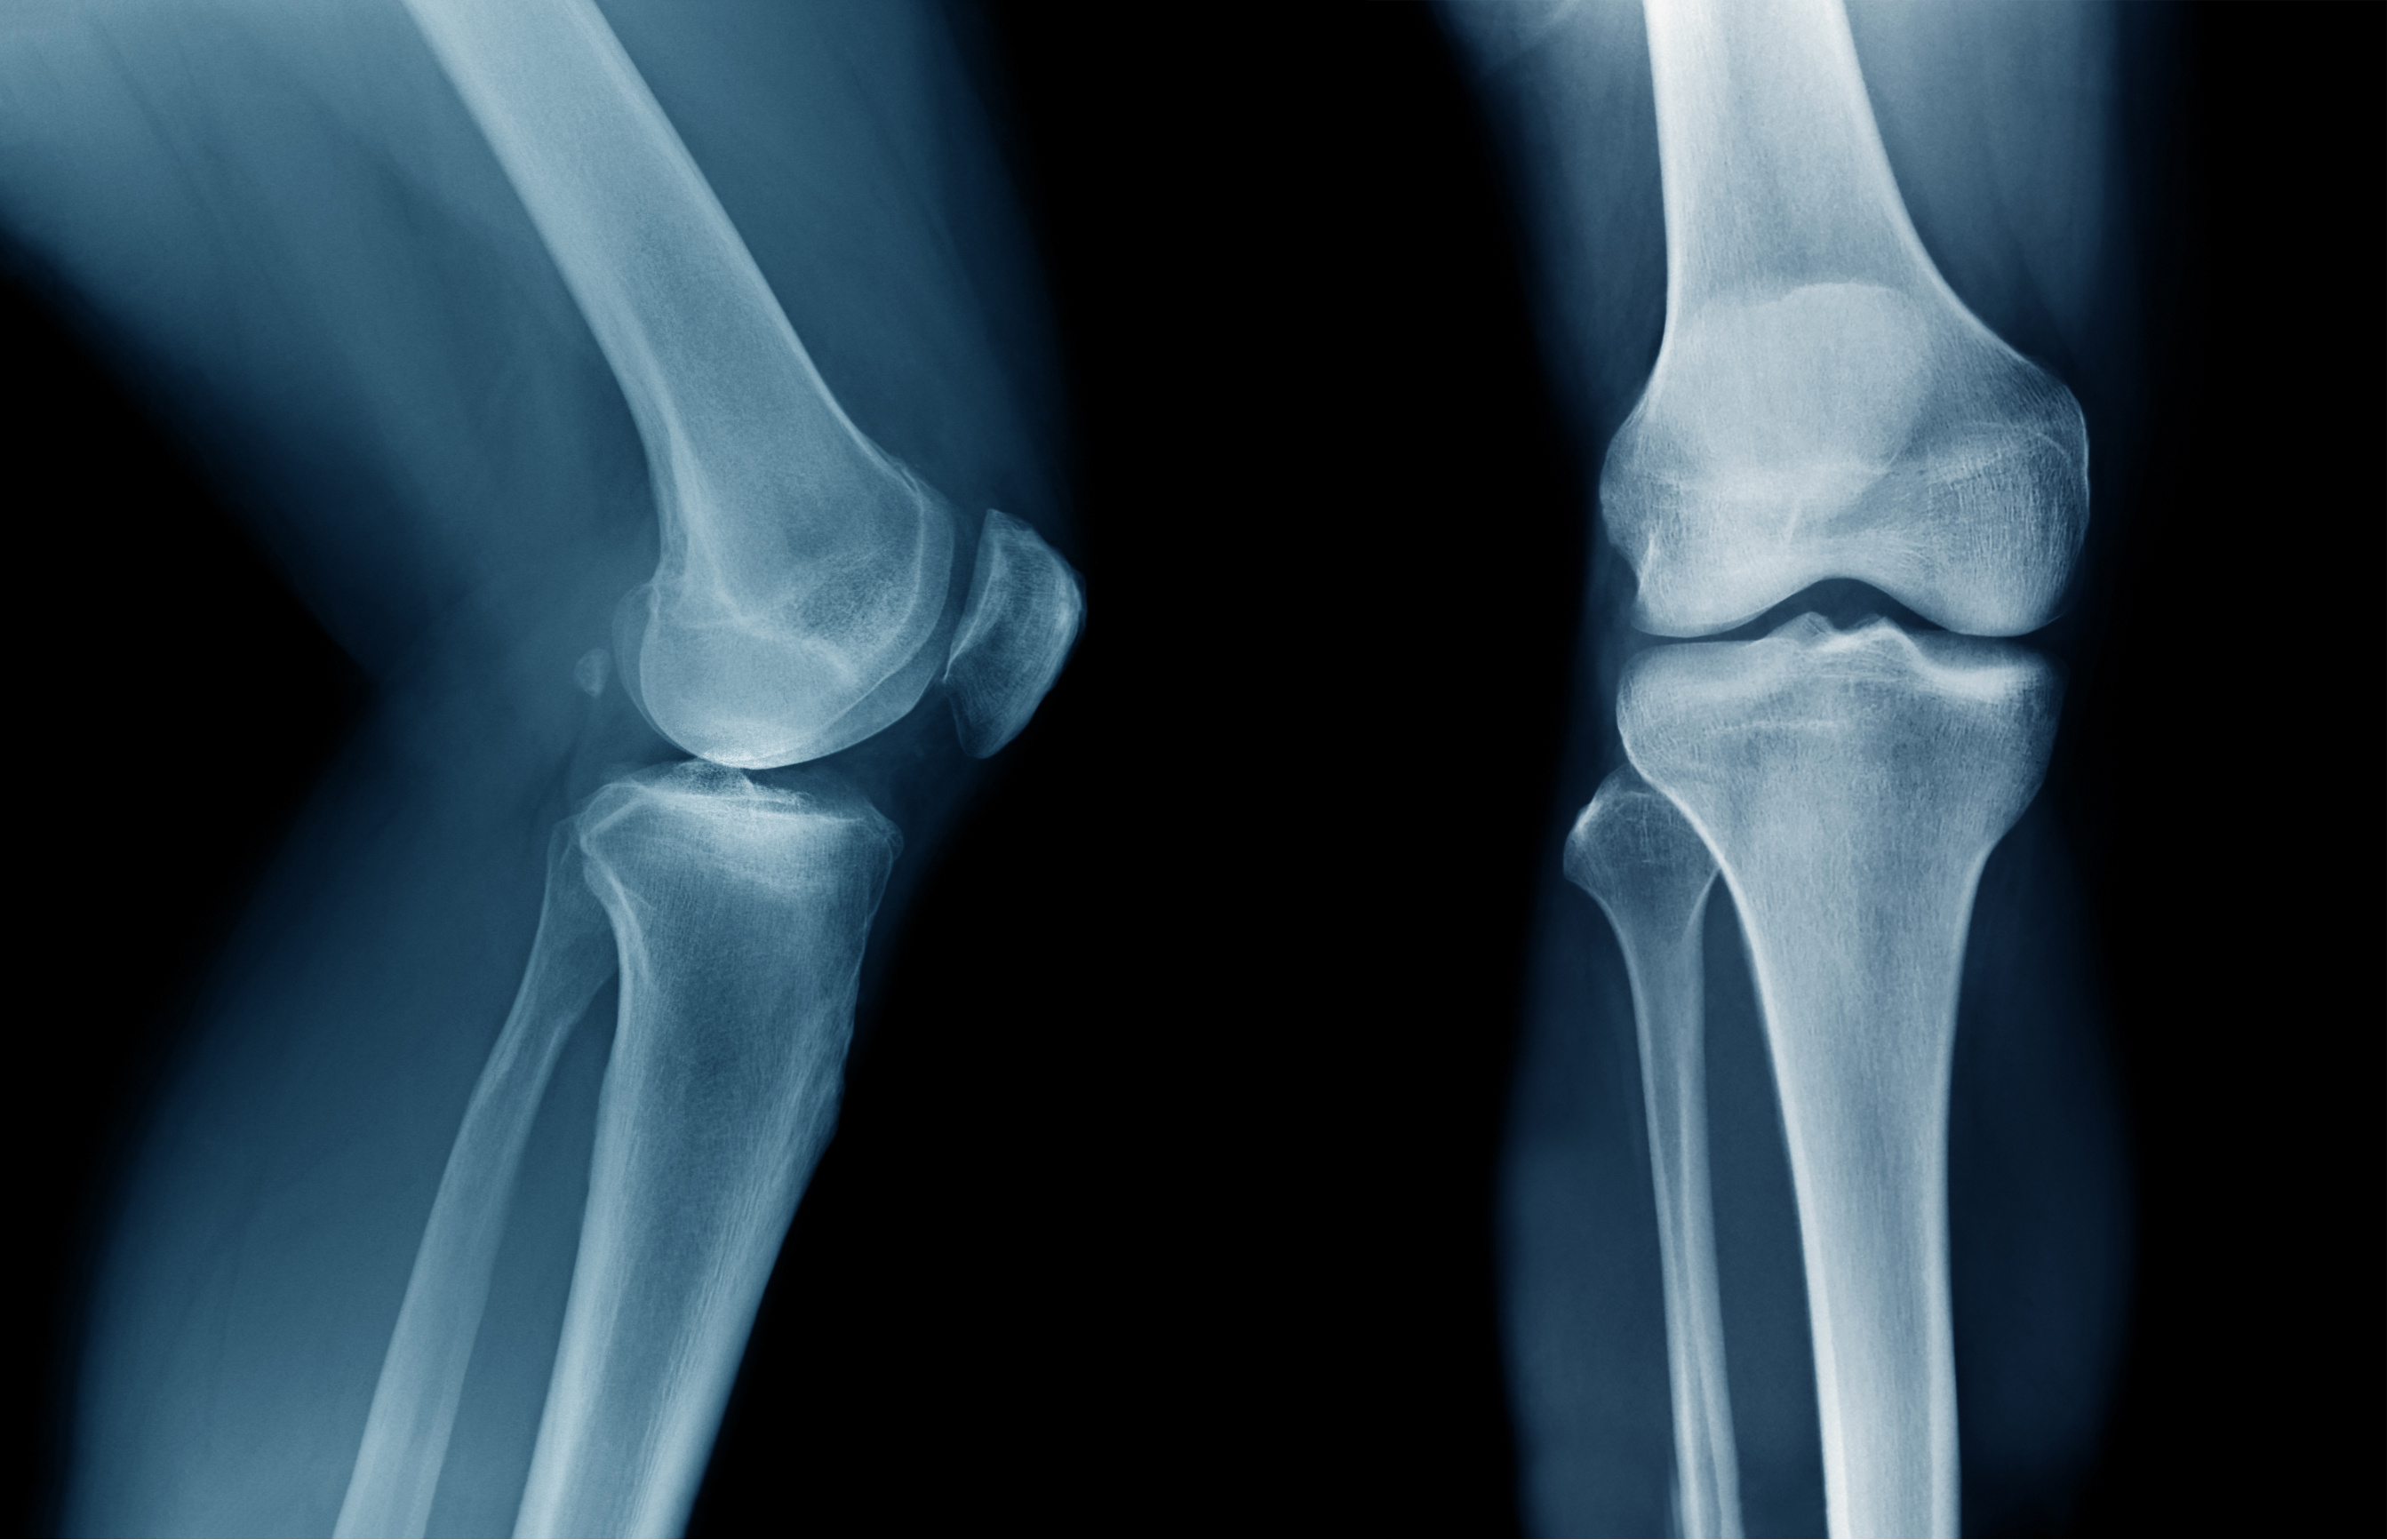

I have plenty of anxiety to talk about. Over the past few years, my knees have been getting worse and worse. At first, it only affected my balance, which was enough to make me anxious right there, fearing that I would fall in public. I started using a cane. I did fall once, at a student union where my therapist’s office was located. A flock of young women (nursing students?) swooped in, picked me up, and offered me a hot beverage. Ever since, my anxiety about falling has increased, exacerbated by a couple of falls at home.

Now, however, I’m facing more serious anxiety. My knees have deteriorated to the point that I need steroid shots every six weeks and am afraid to walk. (The doctor’s words were “bone on bone.”) The steroids work for now but won’t last. Eventually, I’ll have to get both my knees replaced. And that ramps up my anxiety to new levels.

The orthopedist says I could need the knee replacements anytime from six weeks to six years from now. So, of course, I’m anxious that it will be sooner rather than later. I’m catastrophizing, envisioning weeks lying immobile on the couch, taking pain pills, and unable to care for myself. I understand that the doctor said it might not happen for years, but I’m reacting as if it will be next month.

To me, this is Big Life Stuff, and not just because it’s a major operation (two actually, one for each knee). I fear losing control of my body. I worry that knee replacement won’t help. I anticipate going downhill rather than improving. It’s not that I don’t trust my doctors. I’m just consumed by anxiety. I’m looking at ads for mobility scooters and fold-out chair-beds for my study. I can’t envision a future in which things will be any better.